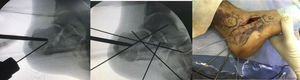

ResultsWe recorded 46 intraarticular fractures in 43 patients (three bilateral). Thirty five were male and eight were female, with a mean age of 42 years (18−79) and a mean follow-up of 57.39 months (33–129). In all cases preoperative CT was performed resulting in: 11 Sanders type II, 23 type III and 12 type IV cases (Table 2). With regard to surgical technique, a standard “L” shaped approach and osteosynthesis with low-profile blocking plates was used in 21 patients (12 Sanders type IV patients and 9 Sanders type III patients), in 10 cases a minimally invasive approach was used of the sinus tarsi (10 Sanders type III cases: four cases synthesized with cannulated screws and six cases with ad hoc anatomical plates with/without cannulated screws (Figs. 1 and 2) and in 15 cases we decided to use an indirect reduction and percutaneous fixation with cannulated screws (11 Sanders type II and four Sanders type III cases) (Fig. 3 ) (Table 2).